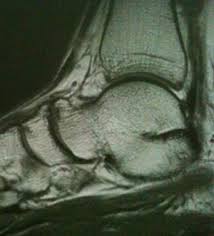

Andere Erkrankungen der Füße entstehen durch Krankheiten die viele Bereiche des Körpers betreffen wie Diabetes mellitus Gicht oder andere Arthritisformen. Die Knochen des Fußskeletts werden durch zahlreiche Bänder zusammengehalten und sind durch Gelenke miteinander verbunden. Alle von diesen Cookies erfassten Informationen werden aggregiert und sind deshalb anonym.

Den gesamten Komplex bilden außerdem Gelenke Fußwurzelgelenke Gelenke der Mittelfußknochen und Zehengelenke viele für die. Eine weitere Ursache für Schmerzen an der Fußaußenseite ist die Fraktur des fünften Mittelfußknochens. Der menschliche Fuß besteht aus 26 Knochen.

Den gesamten Komplex bilden außerdem Gelenke Fußwurzelgelenke Gelenke der Mittelfußknochen und Zehengelenke viele für die. Die Basen der Mittelfußknochen werden darauf mit der Fußwurzelknochenreihe mit Schrauben versorgt. Hühneraugen und Schwielen sind dicke harte Hautpartien die sich häufig an der Seite deiner Füße und Zehen entwickeln. Andere Erkrankungen der Füße entstehen durch Krankheiten die viele Bereiche des Körpers betreffen wie Diabetes mellitus Gicht oder andere Arthritisformen. Den gesamten Komplex bilden außerdem Gelenke Fußwurzelgelenke Gelenke der Mittelfußknochen und Zehengelenke viele für die. Das untere Sprunggelenk verbindet das Sprungbein mit den Knochen der Fußwurzel und dem Fersenbein. Sie unterstützen uns bei der Beantwortung der Fragen welche Seiten am beliebtesten sind welche am wenigsten genutzt werden und wie sich Besucher auf der Website bewegen. Trochanter grch der Rollhügel sd am Oberschenkelknochen. Fuß- und Knöchelbrüche sind recht häufig.